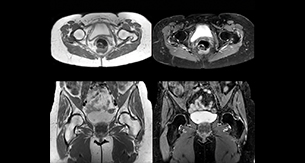

“For bone assessment near joints, mDIXON TSE provides the visualization and multiple contrasts to describe abnormalities within a limited number of acquisitions. Bone marrow signal abnormalities are common MRI findings that can represent various underlying causes, from normal variance to malignancy. So, it is important for us to notice and characterize these findings. With different contrasts, both with and without fat signal as mDIXON TSE efficiently provides, we can make a confident diagnosis.” “Other examples in bone are the signal description of a necrotic fragment in osteonecrosis, the signal description of tumoral matrix that has different components (necrosis, hemorrhage, cartilage, bone formation). These are all possible thanks to in-phase and water images from a single mDIXON acquisition.”

“In peripheral joints, mDIXON TSE imaging aids in diagnosing injuries in ligaments or tendons, for imaging degenerative and inflammatory pathologies such as osteoarthritis and rheumatologic disorders and for oncological exploration.” “For tendon and ligament assessment around knee, ankle, hip and elbow, mDIXON TSE contributes to diagnostic confidence thanks to having images both with and without fat suppression – and without time penalty. This is possible because 2-point mDIXON is faster than the common 3-point Dixon method. It can also increase efficiency as it helps avoid having to add scans during the exam.”

“In peripheral joints, we get good image quality in difficult areas with mDIXON TSE.

Fat suppressed images appear homogeneous over the entire image, even with large coverage at 3.0T – for instance in scapular or hip girdles – or in the bearing areas or around metal prostheses, where fat suppression is often deficient with STIR or spectral fat suppression, causing diagnostic difficulties. If a diagnostic image is right the first time, we don’t need to repeat or add a sequence.” “mDIXON TSE sequences allow simultaneous characterization of morphological changes from the in-phase T2-weighted images and visualization of edematous changes, thanks to the water T2-weighted images from the same acquisition. Anatomical and morphological considerations could be a partial or complete ligament tear, a bony avulsion or hematoma.” “For soft tissue assessment mDIXON brings similar benefits. For example in one T2-weighted mDIXON TSE acquisition, having the multiple contrasts helps us assess abnormalities in peripheral nerves fascicles, which may be due to anatomical or inflammatory changes..”